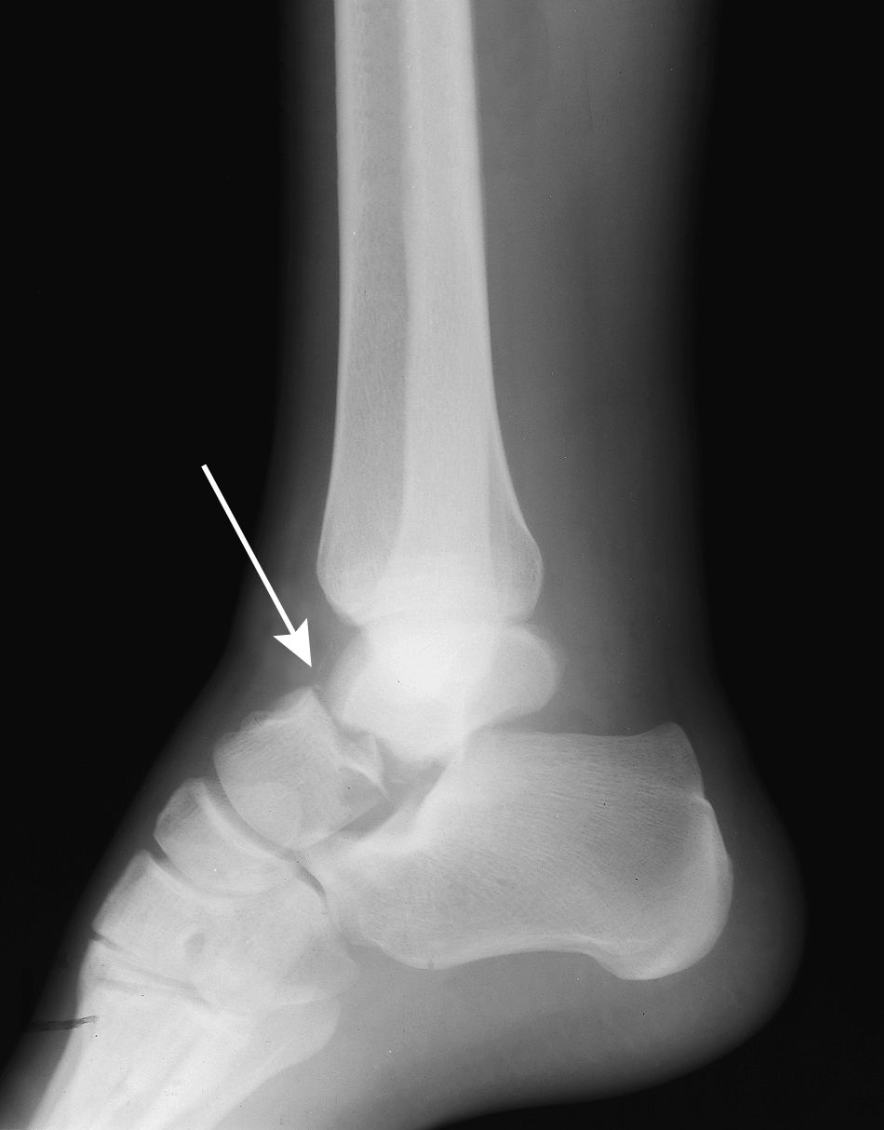

History of repeated ankle trauma, pain with weight bearing, intermittent swelling, catching and snapping, the dome of this bone is tender upon palpation. Two words in the name.

Talus Fracture